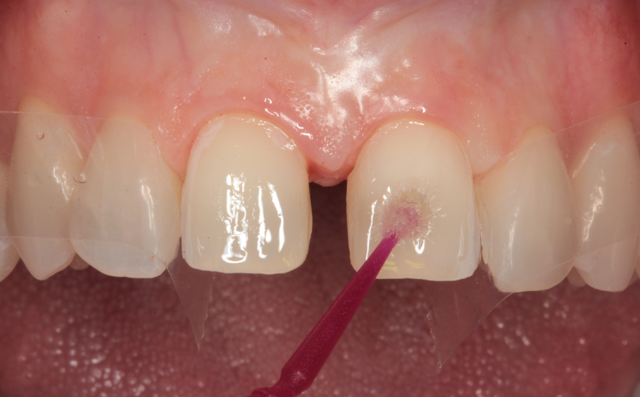

Bonding agent (Prime & Bond NT, Dentsply/Sirona) was applied to the prepared surfaces (Fig. 13) and air thinned (Fig. 14). The bonding agent was light cured for ten seconds with a LED curing light (Fig. 15). Veneer cement (Calibra Veneer, Dentsply/Sirona) was applied to the silane treated internal surfaces (Fig. 16).

Fig. 13 Fig. 14 Fig. 15